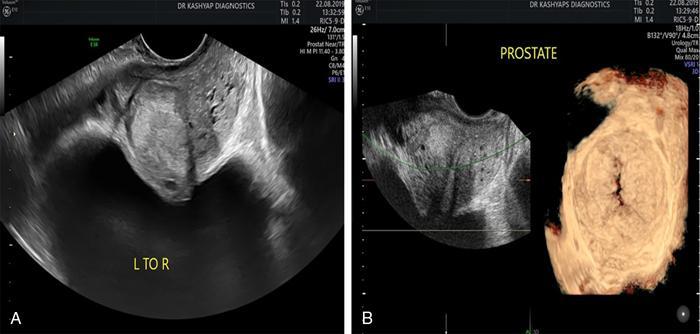

Benign prostatic hyperplasia